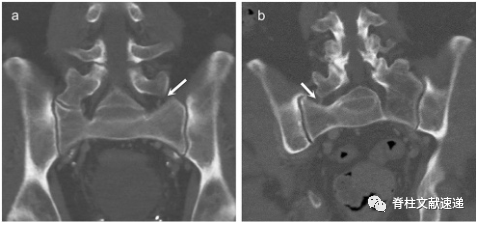

近期,Hanhivaara J等人的研究更是通过CT结果提出了LSTV的新的亚型,IIc型和IIIc型(如图4)。

图4:a:63岁男性患者,右侧假关节形成,左侧横突增宽超过19mm但无关节形成(箭头所示),Hanhivaara J将其定义为IIc型LSTV。b:78岁男性患者,左侧完全融合,右侧横突增宽超过19mm但无假关节形成,Hanhivaara J将其定义为IIIc型LSTV。